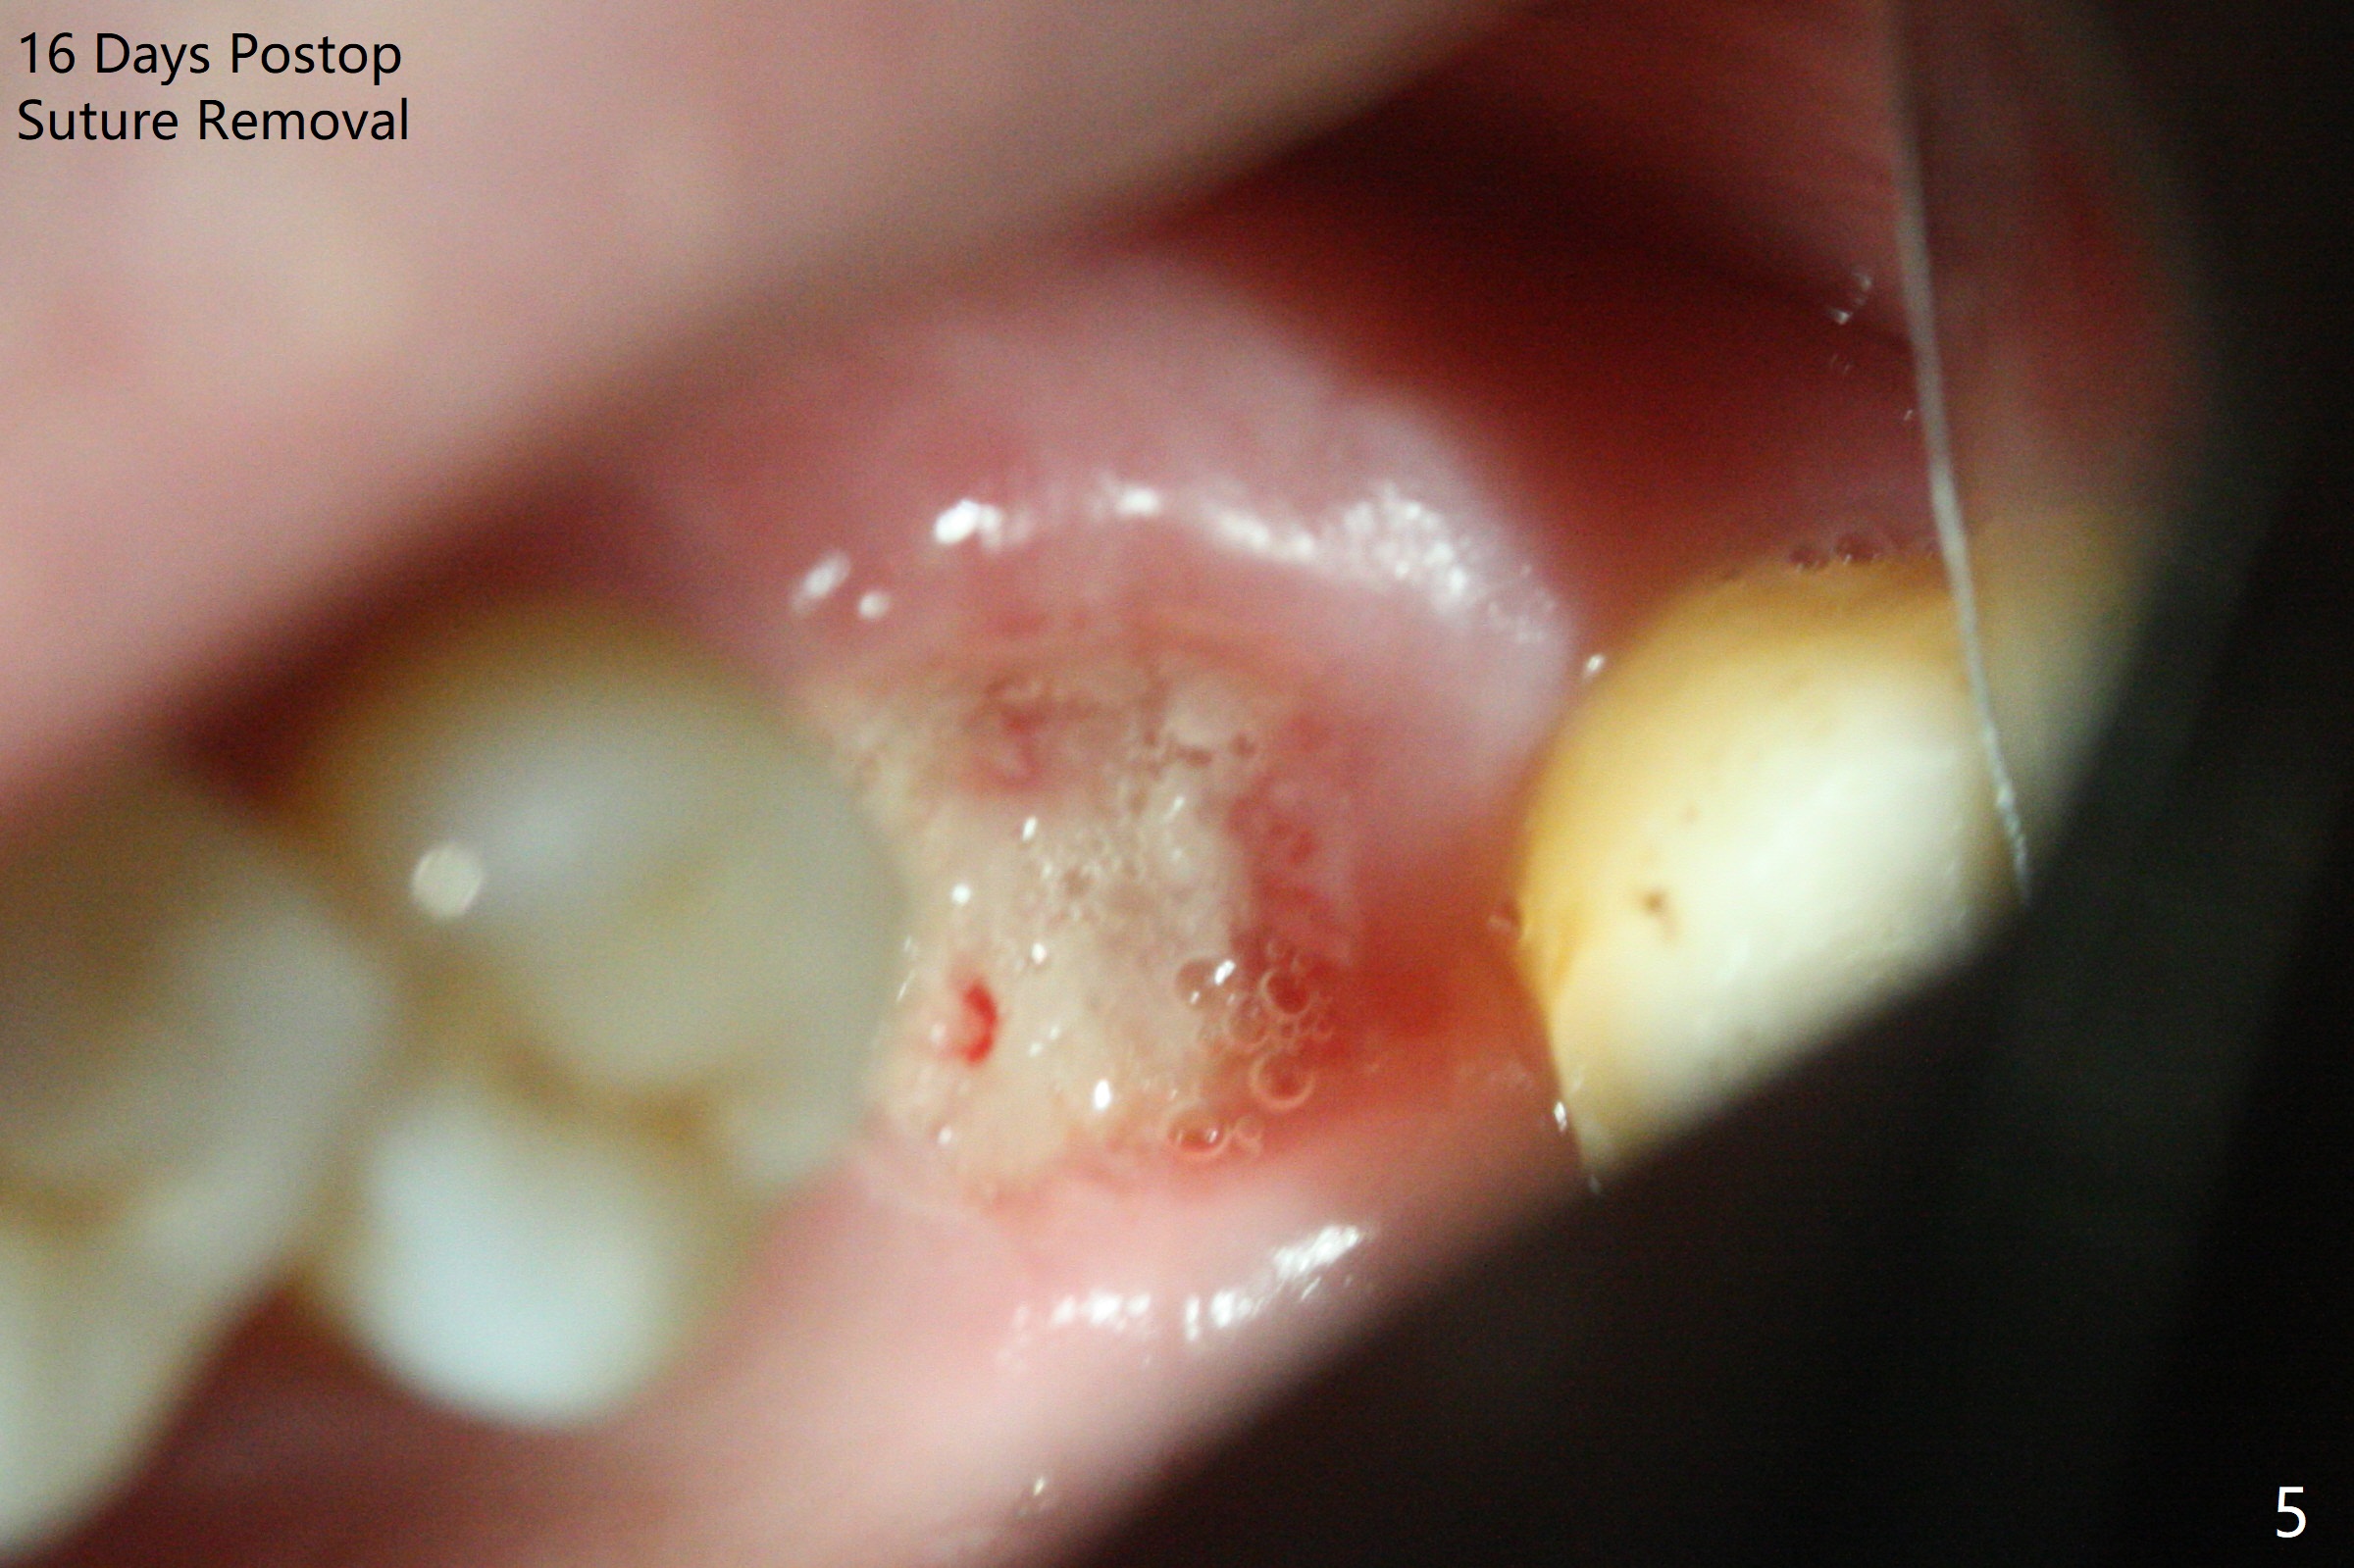

67岁女深洗后突然回来要求拔除左上六(图一),颊侧红肿,流脓,牙周袋深(图二B),经过多番劝导,终于图一植骨,由于时间仓促,使用合成血小板生长因子(GEM21S,而不是PRF))与皮质骨(125μm – 850μm)以及皮松质骨(500μm – 1,000μm)调拌,放置于巨大吸收融合颊侧牙槽窝(图三*(无颊侧骨板)(使用condenser)),而腭侧牙槽窝没有明显破坏(图一P),放置Osteogen Plug(一种骨胶原, 图三 O)。牙槽窝口放置胎盘膜(BioXclude),使用4/0 PGA缝线。傍晚病人已经 没有肿痛了。术后十三天牙周敷料脱落,伤口愈合良好。三天后病人又回来复诊(图四),折线后,虽然伤口愈合,骨粉好像填的不够多(图五),或者丢失。树脂敷料可能取得更好的结果。